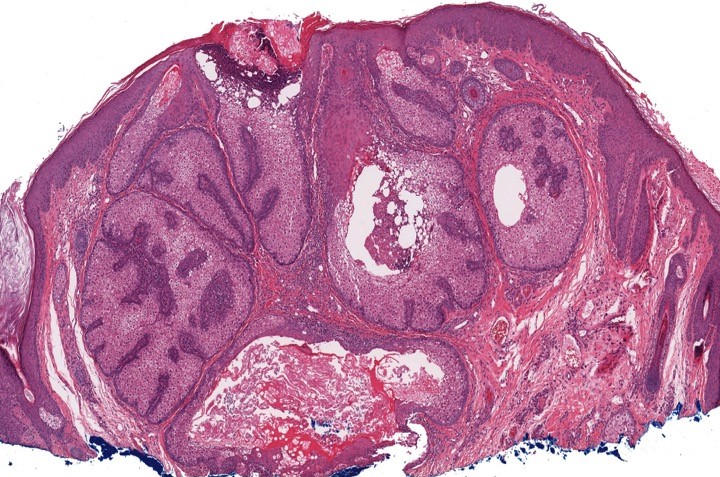

Microscopic (histologic) images

- Well circumscribed, nodular growth of lobules consist of admixture of basaloid cells and mature sebocytes

- Some lobules may communicate directly with the surface epithelium

- Basaloid cells are usually located at the periphery of lobules and sebaceous cells with intracytoplasmic lipid vacuoles, which are usually located at the center of lobules

- Basaloid cells are composed of expanded germinative layer, with more than the normal 2 cell layers seen in mature sebaceous glands or sebaceous hyperplasia but still less than 50% of the tumor volume (> 50% is seen in sebaceoma / sebaceous epithelioma)

- Well circumscribed superficial dermal nodule with sharp demarcation from the underlying tissue